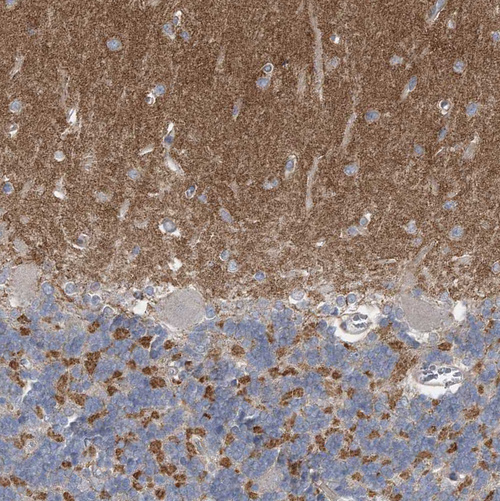

Immunohistochemical staining of human cerebral cortex shows strong positivity in neuropil.